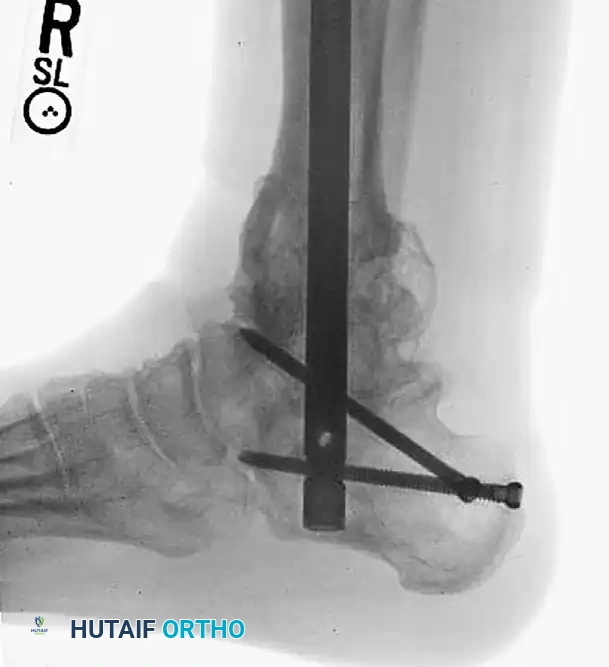

Preoperative radiograph demonstrating a highly comminuted fracture of the tibial pilon following a fall from a height. Note the preexisting posttraumatic arthritis of the tibiotalar and subtalar articulations secondary to a previous talar fracture.

In such complex scenarios, a primary tibiotalocalcaneal (TTC) arthrodesis utilizing a retrograde intramedullary nail provides rigid stabilization of the fracture while simultaneously addressing the arthritic joints, allowing for early mobilization.